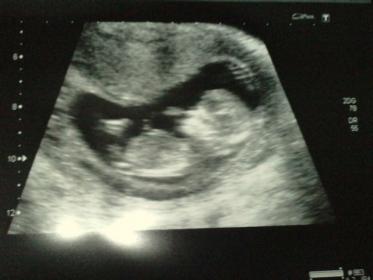

Hi All, just had 12 week ultrasoundm would luv to know what you all think.....

Girl

Girl 💗👶

I'm very new to this whole nub guessing, but what I have researched I would guess girl :)

leaning boy.

lean boy as well

boy? Not too sure though!

possibly boy but wouldn't be surprised by girl either.